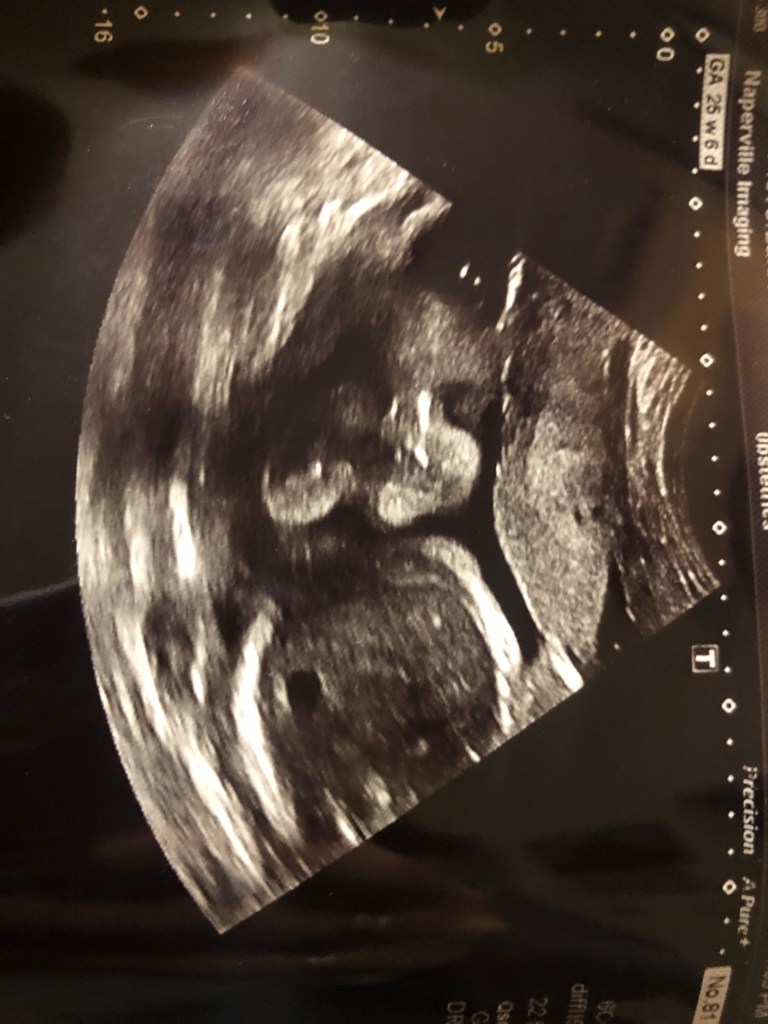

This soon-to-be-here newest addition is the reason I haven’t updated our farm page. When I’m pregnant, I become a recluse and don’t like to put effort into anything that I don’t have to. So, the past 7 months have been spent doing what needs to be done and avoiding a bunch of everything else. The creative side of me steps aside temporarily for the reality based side. Either that or I have a serious case of pregnancy brain fog… I’m not sure. But my love of writing has become a chore.

Anyhow, we are looking forward to meeting our new baby boy or girl, and will update as the fog clears 😉.